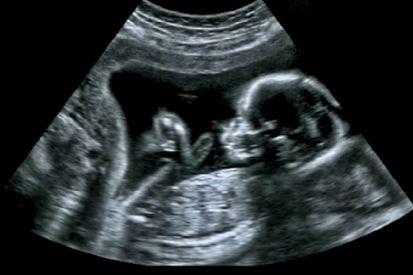

Van Noor1993 In Geslacht van je baby